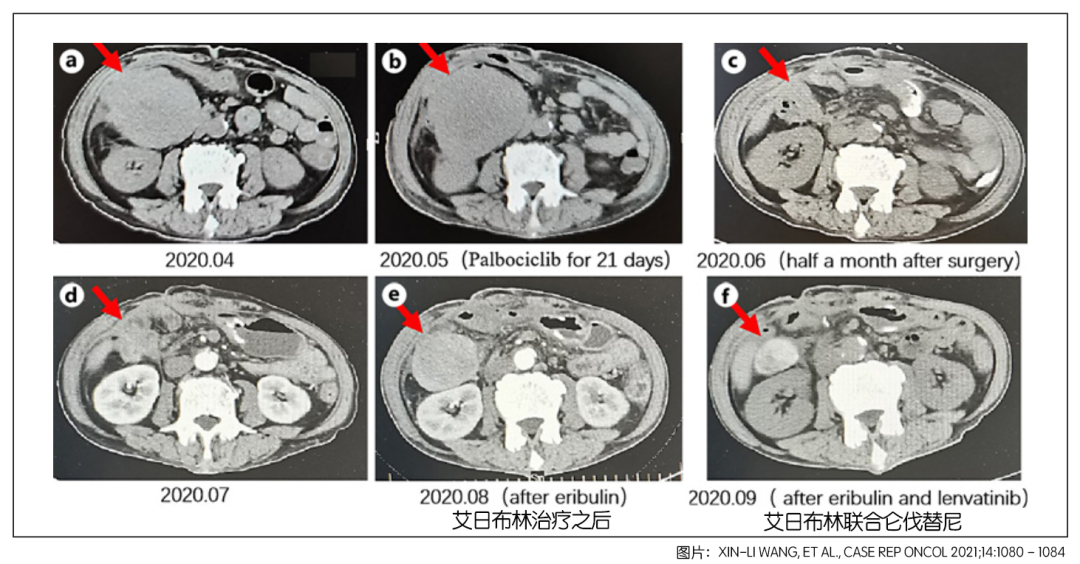

图1.患者治疗不同时期的CT影像学检查结果

几个月之后,患者因为大便带血再次入院,身体情况很差。经过对手术的组织样本进行二代基因测试发现存在CDK4/6基因扩增。这个基因突变的概率高达90%,为此给予了帕博西林进行治疗,使用了21天之后,患者的左肺出现了一个新的结节。

由于反复便血,2020年5月15日,患者再次进行了腹部巨大肿瘤切除,同时进行了部分肠、胆囊切除,以及肠粘连解除术。很不幸,手术后一个月,患者的腹腔再次出现了复发。不得已给予两个周期的艾日布林进行治疗,但病情并未得到控制,依旧进展。

综合考虑患者病情后,医生决定联合用药:艾日布林联合仑伐替尼,艾日布林每天2毫克,仑伐替尼每天8毫克。联合用药方案终于凑效了,最近的腹部检查发现肿块明显缩小,肺部结节减少,临床评估为病情稳定。

图2.患者治疗不同时期的腹部CT影像学检查结果